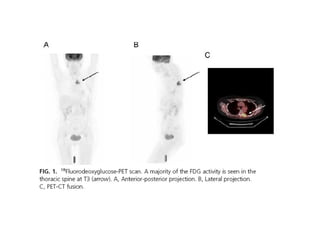

   Taieb, D. (2011). [18F] Fluorodeoxyglucose positron emission

tomography in advanced thyroid cancer. Medicine Nucleaire ,

329-331.

• 76.

Soo-Youn An, K. H. (2010). Surgical management of locally advanced thyroid cancer. Current Opinion in Otolaryngology and Head and Neck Surgery , 119-123.  Taieb, D. (2011). [18F] Fluorodeoxyglucose positron emission tomography in advanced thyroid cancer. Medicine Nucleaire , 329-331.  Urken, M. L. (2010). Prognosis and Management of Invasive Well-differentiated Thyroid Cancer. Otolaryngol Clin N Am , 301-328.  Yassine Lalami, A. A. (2011). Recurrent thyroid cancer: a molecular-based therapeutic breakthrough. Current Opinion in Oncology , 235-240.